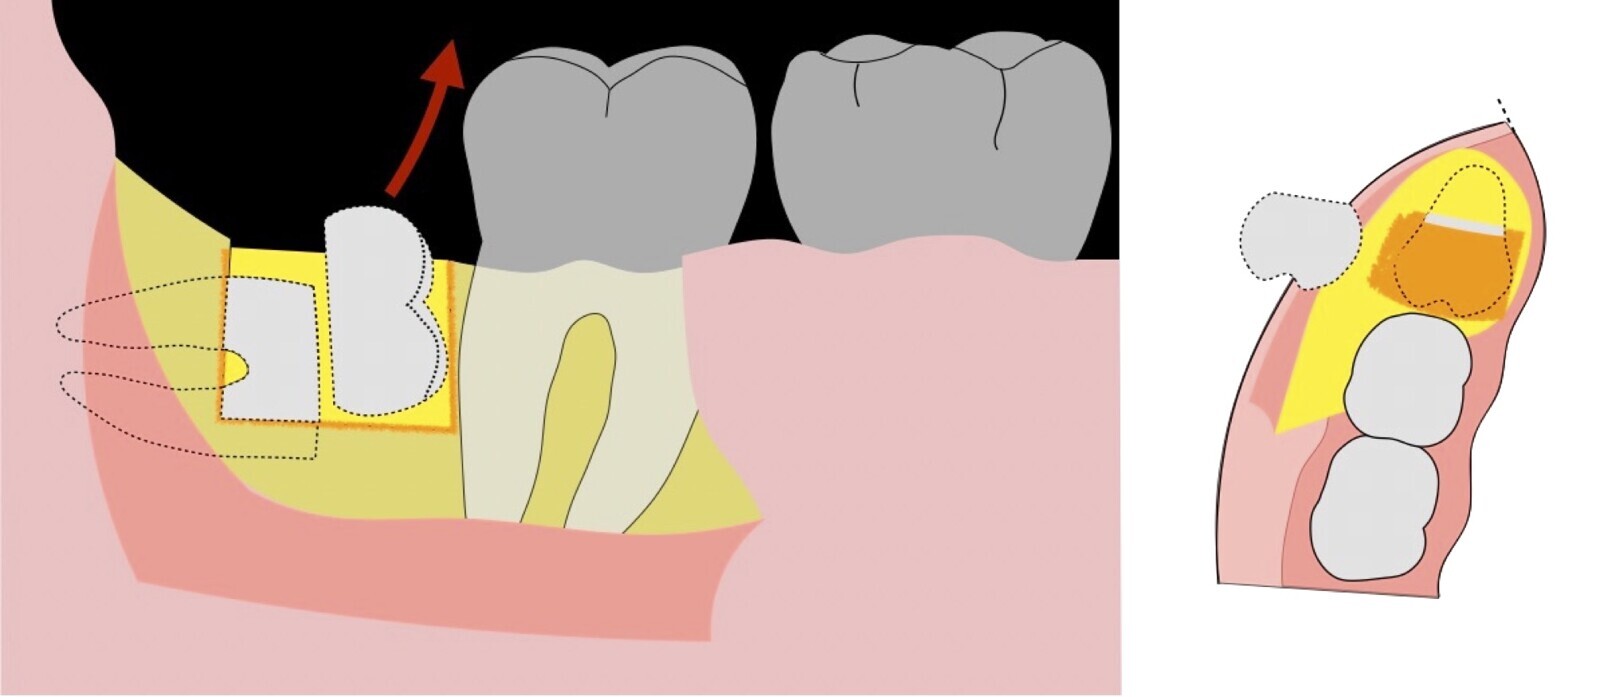

Figura 10. Tracción mesial del remanente dentario utilizando botadores en bandera.

Figura 11. Avulsión del remanente radicular de la tercera molar.

Figura 12. Eliminación del capuchón pericoronario y verificación del lecho óseo posterior a la exodoncia.

Figura 13. Afrontamiento del colgajo y sutura.